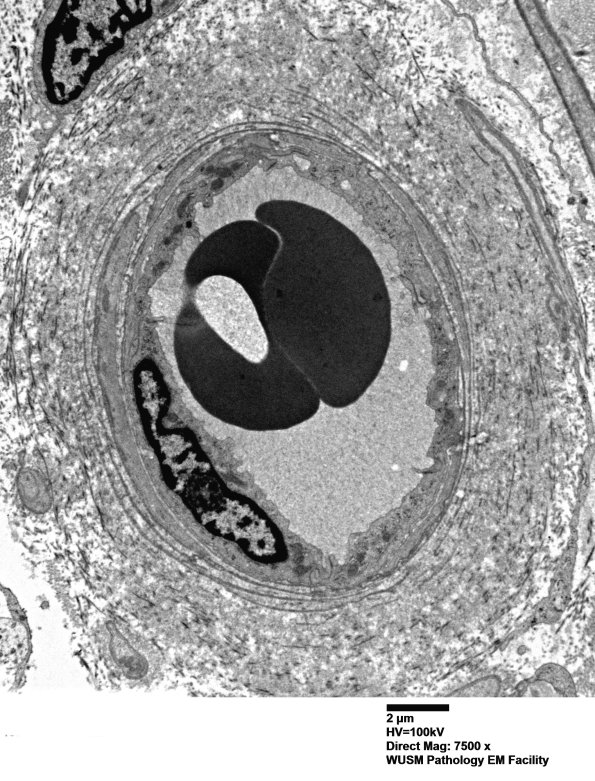

17B4,5 An additional example of mild vascular enlargement. (electron micrographs)